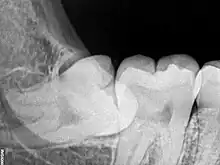

Lorsque la dent bute sur le collet de la deuxième molaire, elle est bloquée dans son extériorisation. On dit qu'elle est « enclavée ».

La dent est dite « incluse » lorsqu'elle est entièrement recouverte par l'os et la gencive, au niveau de la face postérieure de la racine de la deuxième molaire.

Entre 15 et 25 % des dents de sagesse mandibulaires sont incluses ou enclavées[13].